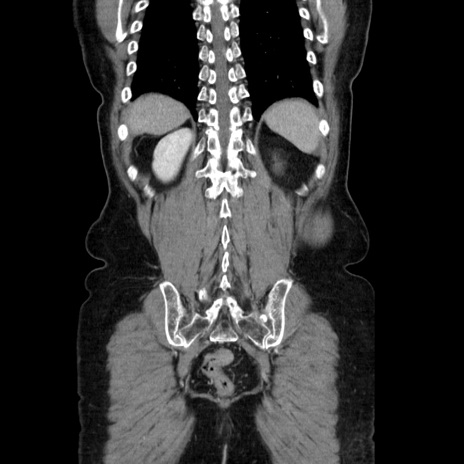

症例5(冠状断像)

【症例】70歳代女性

【主訴】お腹が張る

【現病歴】1週間くらい前から腹部膨満の自覚あり。昨日夜から増悪したため、本日救急外来受診。

【身体所見】意識清明、BT 36.5℃、BP 165/106mmHg、HR 80bpm、SpO2 98%、腹部:膨満、軟、自発痛・圧痛なし、触診にて不快感あり、腸蠕動音:減弱

【データ】WBC 12600、CRP 1.04